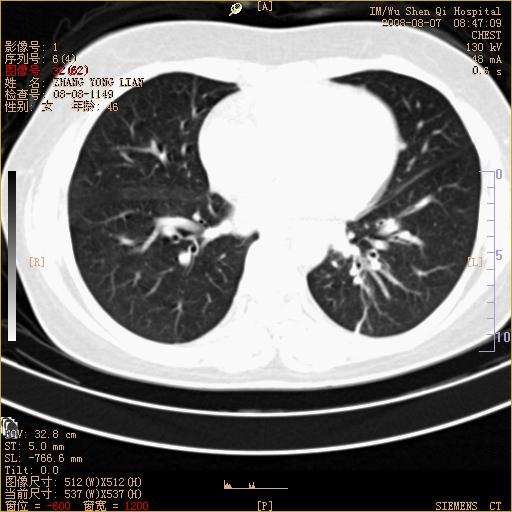

标题: CT15050:女,46岁,咳嗽胸痛一月余 [打印本页]

纵隔窗没发全,左下肺近胸膜处结节。有长毛刺,纵隔淋巴结增大,不排除恶性病变。

考虑肺癌

考虑左肺下叶后基底段周围型肺癌伴纵隔淋巴结转移可能性大。

左下肺ca并纵隔及左肺门区淋巴结转移。

1)考虑左肺下叶后基底段周围型肺癌伴纵隔淋巴结转移。2)脾内低密度灶,性质待定;不排除转移瘤可能。

考虑左肺下叶后基底段周围型肺癌伴纵隔及肺门淋巴转移。